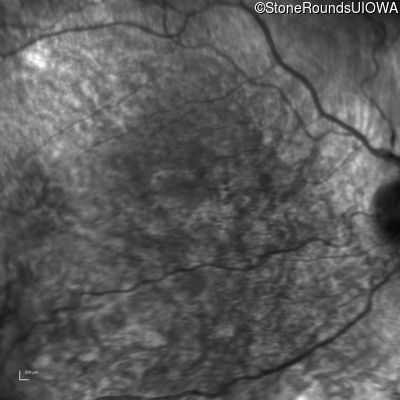

Infrared Fundus Photograph - Right - 20/63 +1

Exemplar